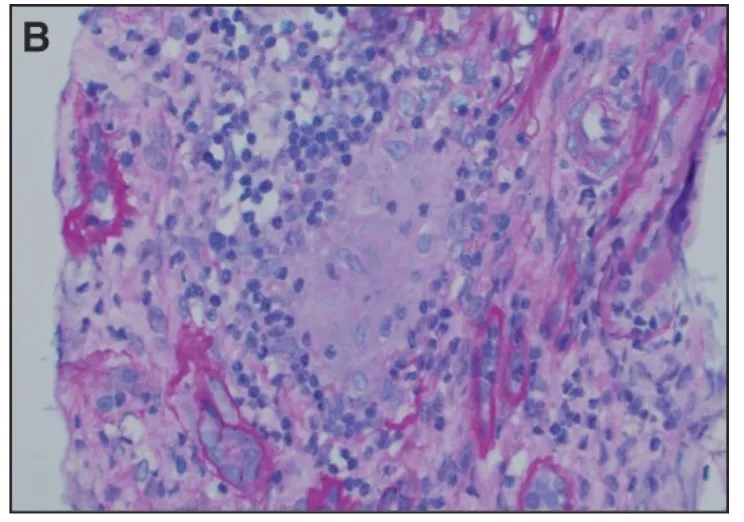

IRA + Icterícia: Um Caso que Exige Investigação Detalhada

IRA + Icterícia: Um Caso que Exige Investigação Detalhada